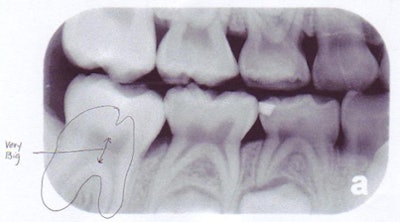

| Above, panoramic x-ray of a 9-year-old shows the mixed dentition typical of someone that age. Below, panoramic x-ray of a 16-year-old shows the formation of third molars. All images courtesy of Sandra Swing, D.D.S. |